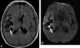

Basilar racemose form of cysticercosis

Cysticercosis is a tissue infection caused by the young form of the pork tapeworm. People may have few or no symptoms for years. [Source: Wikipedia ]